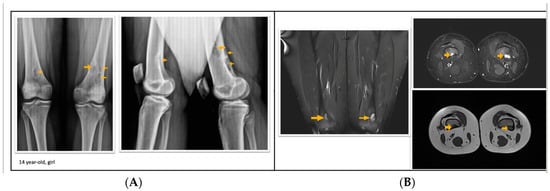

2.2. Radiological Evaluation of FCD/NOF